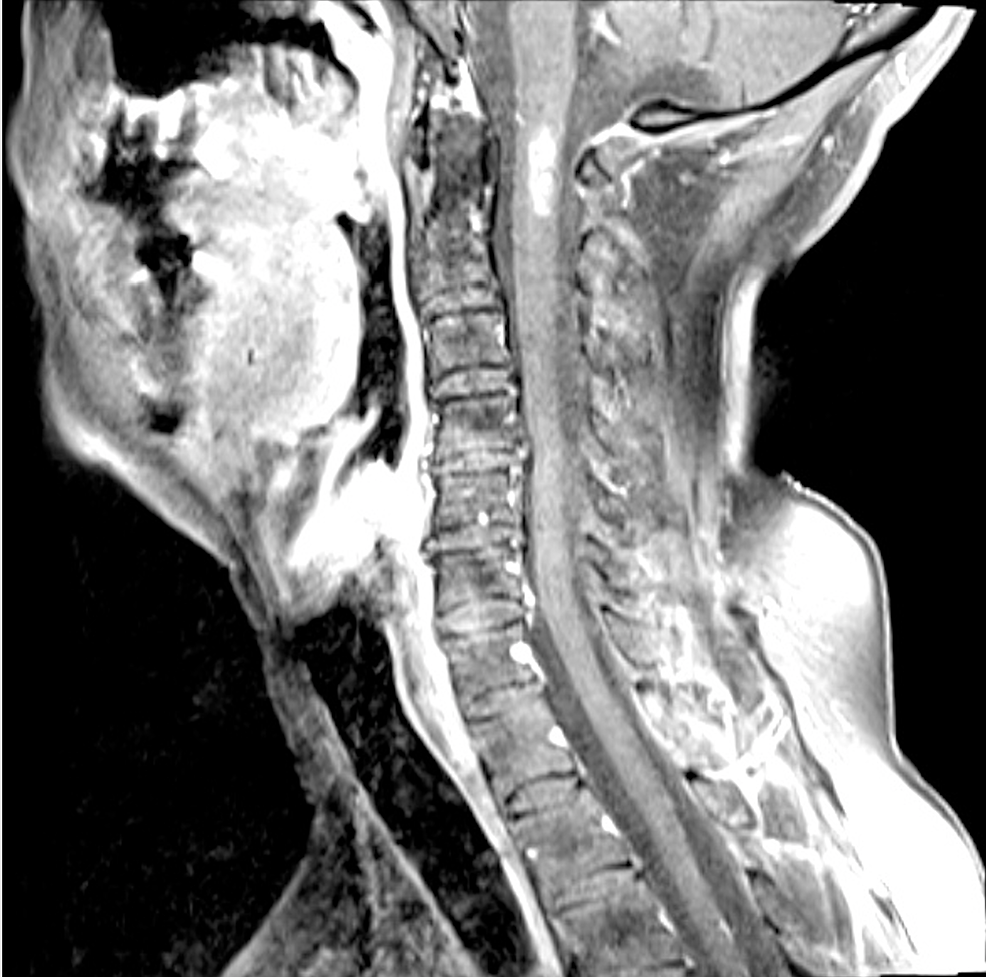

The spinal cord normal anatomy eAnatomy What Is Enlargement Cervical It represents the origin of the brachial plexus. Web the cervical enlargement is a widened area of the spinal cord that supplies nerves to the upper limbs, facilitating motor and. Web learn about the two enlargements of the spinal cord that correspond to the nerve plexuses of the upper and lower limbs. Web learn about the anatomy and functions of. What Is Enlargement Cervical.